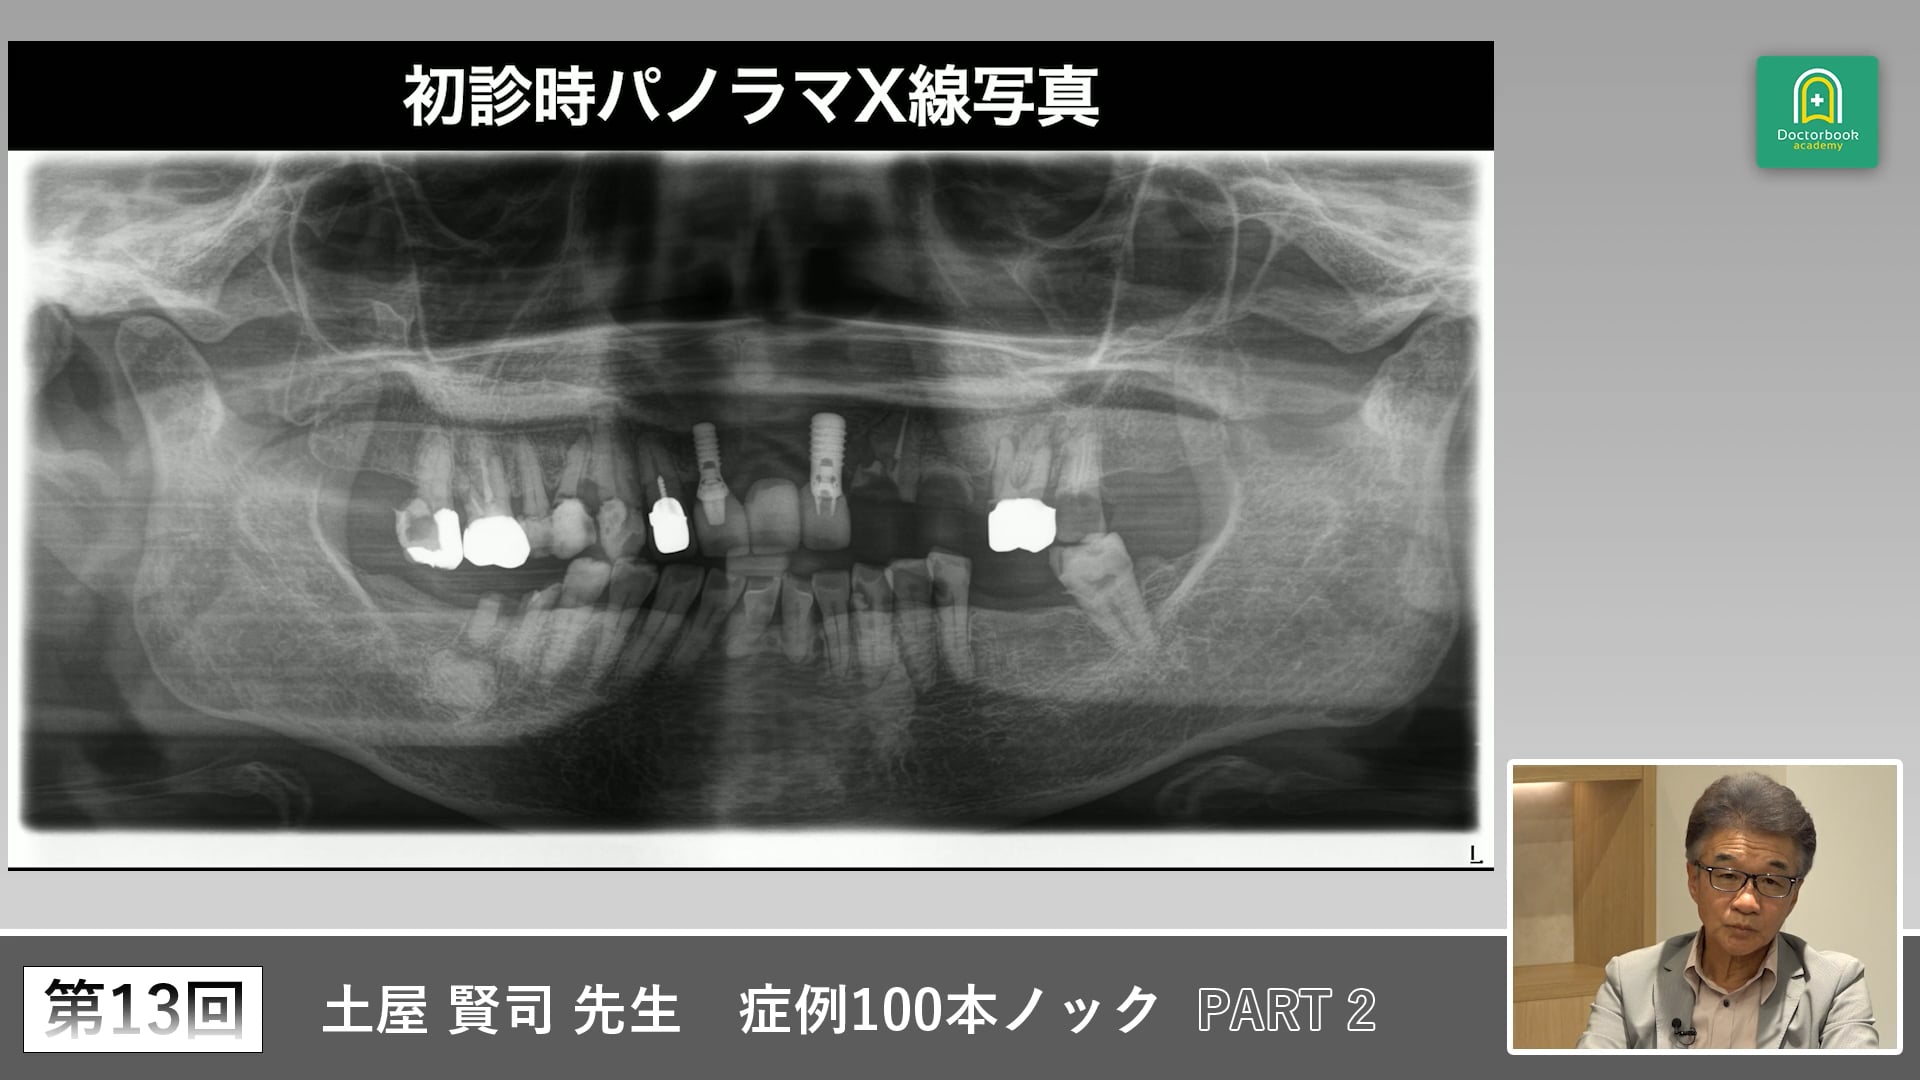

右下の大臼歯部の欠損については、どのような補綴を行うのが最適でしょうか?

このようなすれ違い咬合を呈するような場合には、どのように考えるべきなのでしょうか?

ここで着目すべきは、天然歯の存在です。

今回の症例で、キーとなる歯は左上の6、7です。

この歯を安易に抜歯するのではなく、根面板にしてでも残しバーティカルストップの基準とすべきです。

左側のバーティカルストップの基準は左上6,7にし、デンチャーによって咬合を付与していくと土屋先生は考えます。

すれ違い咬合は難症例となりやすいです。

咬合支持の確立だけでなく、力のコントロールも必要になります。

そうしなければ、残存歯の歯根破折の可能性も出てきます。